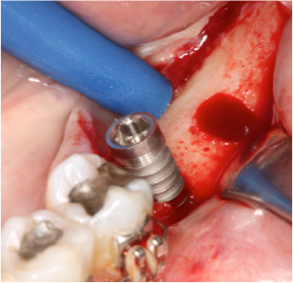

Fig 3, 4 e 5 Observar o posicionamento da broca e o posicionamento do implante com a parte cervical voltada para a lingual e o ápice para vestibular, passando do lado do nervo alveolar.